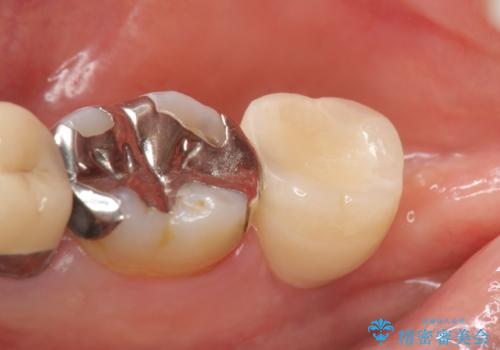

インプラントと骨の定着を待った後に二次手術を行い、カスタムアバットメント、オールセラミッククラウンによる補綴を行いました。

今回用いたオールセラミッククラウンはジルコニアフレームという白い素材の上にセラミックを盛っているため、審美性が非常に高いのが特徴です。

また、ジルコニアは人工ダイヤモンドの材料にも使われているほど高い強度を持っており、そのためオールセラミッククラウンは審美性だけでなく、奥歯やブリッジの補綴も可能とするクラウンです。